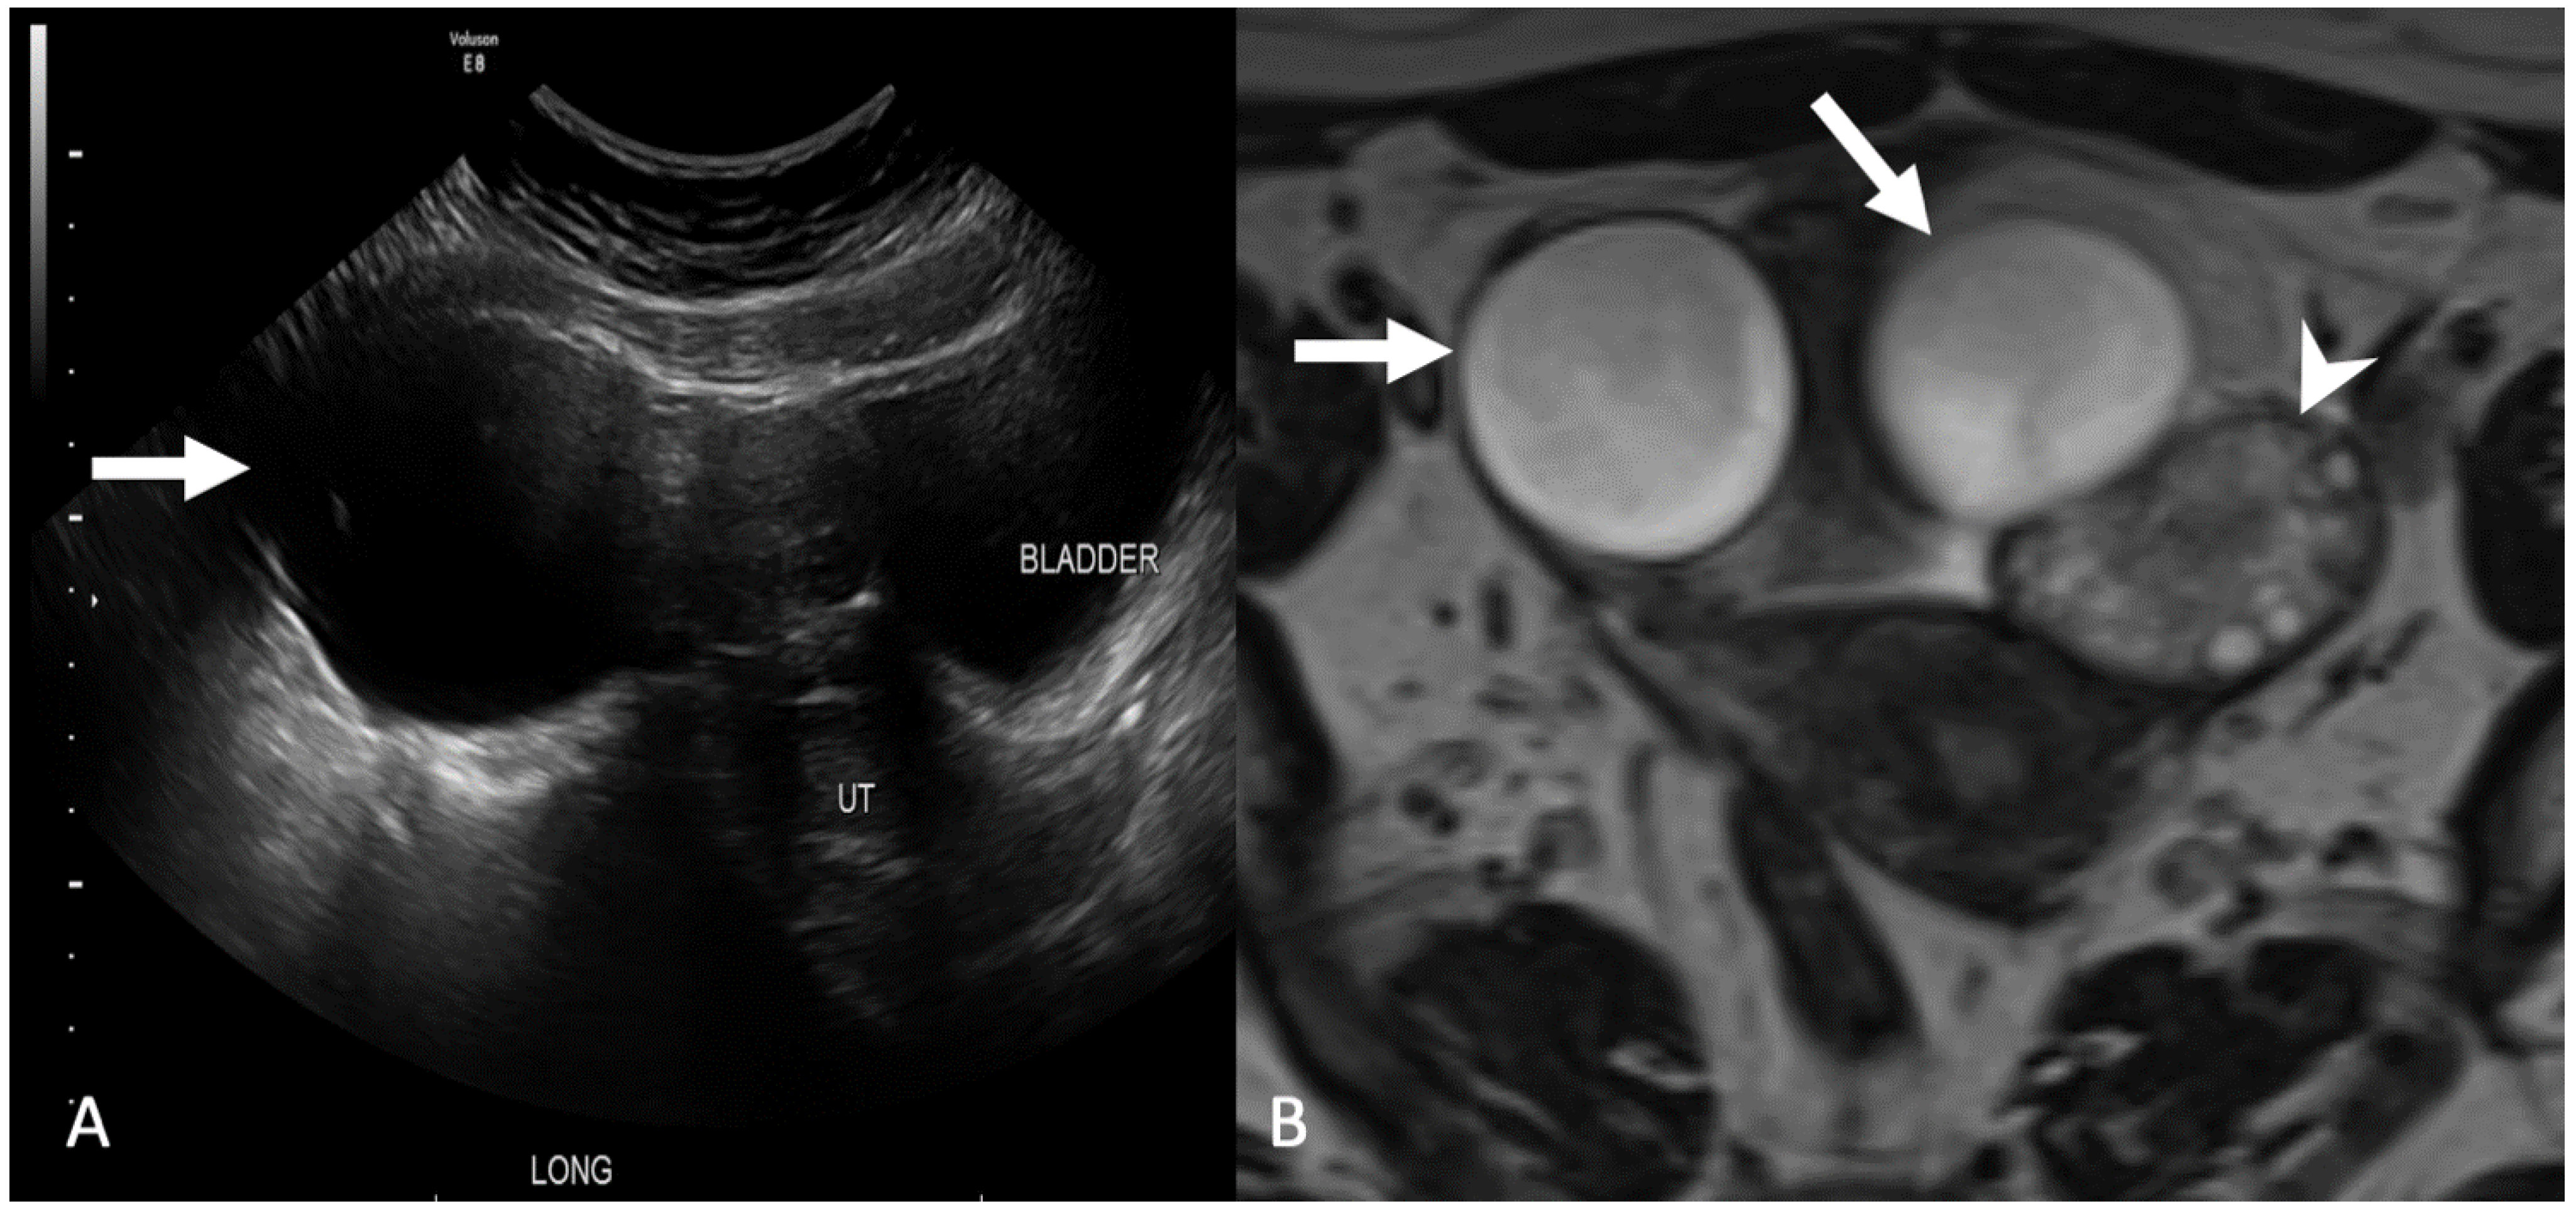

5.2.1. Uterine Vasculature

5.2.2. Leiomyoma